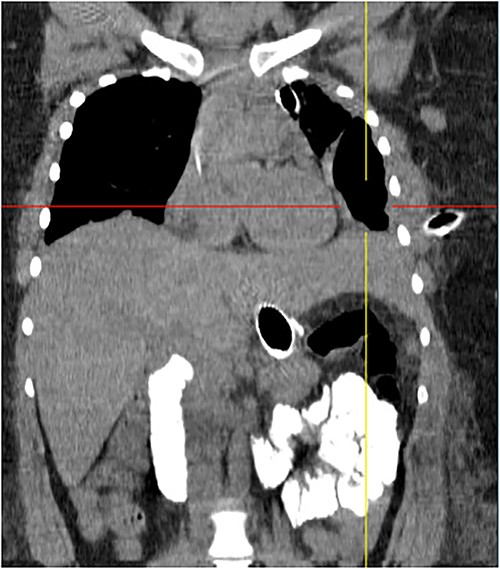

On 19 January 2021, a tomographic control showed leakage from the esophagogastric junction and left-sided pneumonia (Figs 4 and 5). Consultation with the cardiothoracic surgery department led to the decision to perform VATS.

Coronal chest tomography showing the presence of the gastroesophageal stent and the left pleurothoracic cavity.